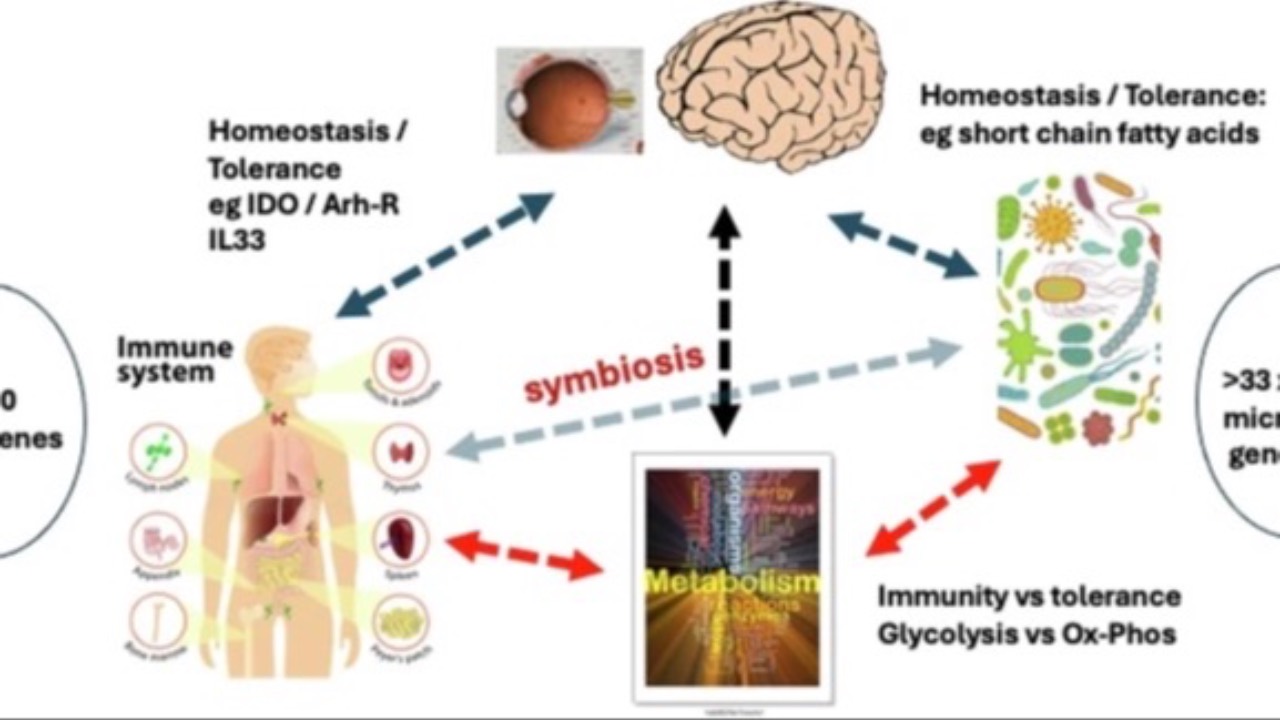

The Story Of Ocular Immunology

The eye on the daily front lines...

The evolution of the ocular immune system is a fascinating journey spanning billions of years. This complex system emerged from primitive cellular responses, with innate immunity taking shape around 2.5 billion years ago.

Over time, the development of adaptive...